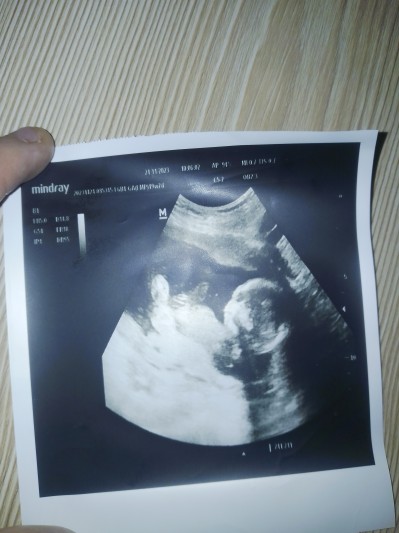

19+2 yim halen belki değil sizce nedir ne gelirse Allah'tan iki kızım var kizlar kusura bakmayın iki post açılmış daha önce hiç post açmadım:) burdan

Kesede duruşu yani kafasının yönunden kız dıye dusunuyorum ınsaAllah saglıklı hayırlı oglandır ♥️ gonlunden o gecıyordur ama nasip

Kiz diyorum cnm netlesince yazarsin

Erkek gibi geldi bana